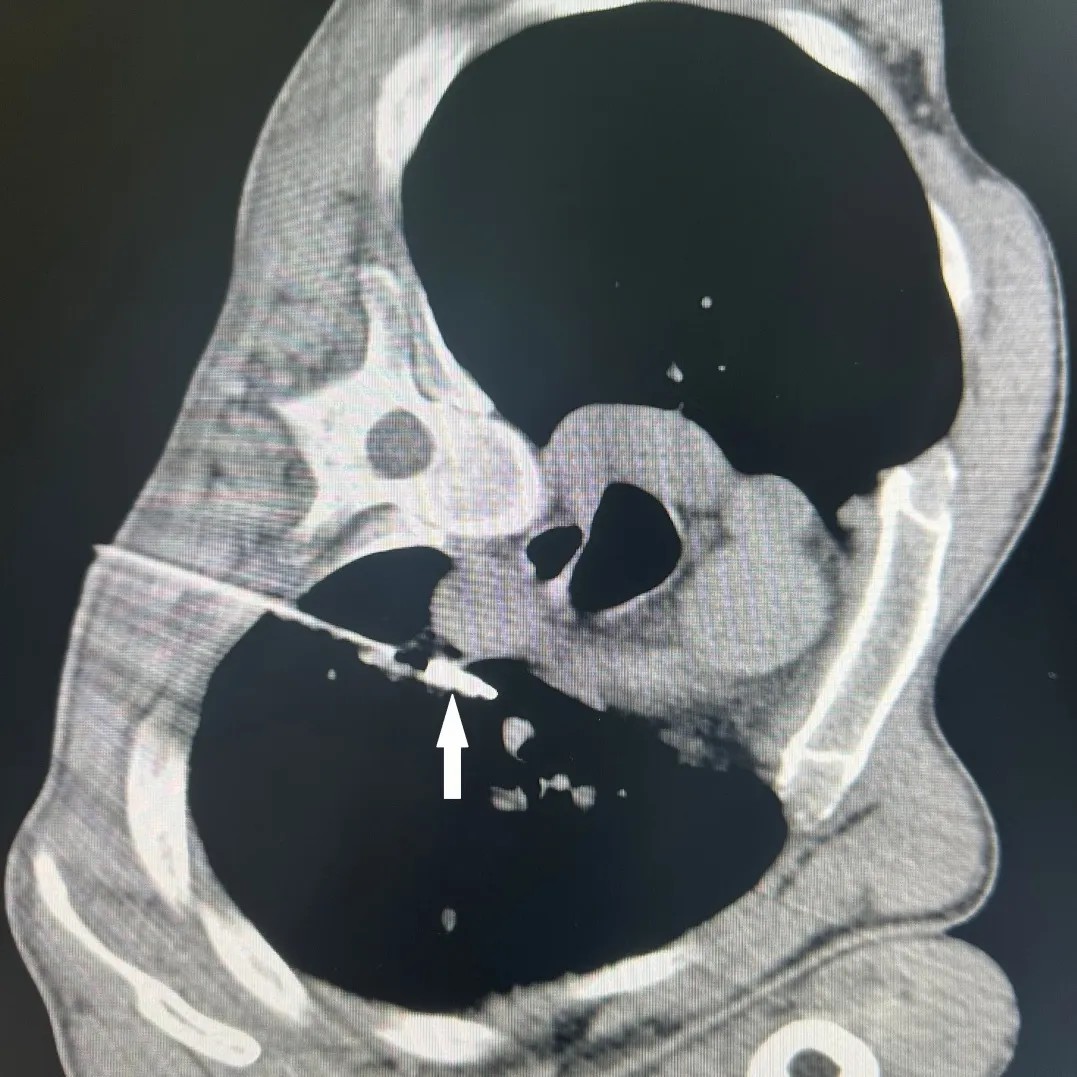

胸部CT显示肺上病灶一个位于肺上叶,因病灶位置较高,肋间隙较窄,比邻肩胛骨,给穿刺造成明显困难;另一个病灶紧邻主肺动脉,穿刺出血风险极高。7月25日,李建军主任经过仔细读片,认真分析,选择了最佳的穿刺路径,通过CT引导,在次旺晋美医师辅助,扎西次仁和德吉卓嘎护士配合下,一次手术对两个病灶进行了精准消融,术后CT扫描显示病灶完全坏死,未出现气胸等并发症,患者安返病房。

微波天线精准穿刺入主肺动脉旁病灶内(白色箭头)